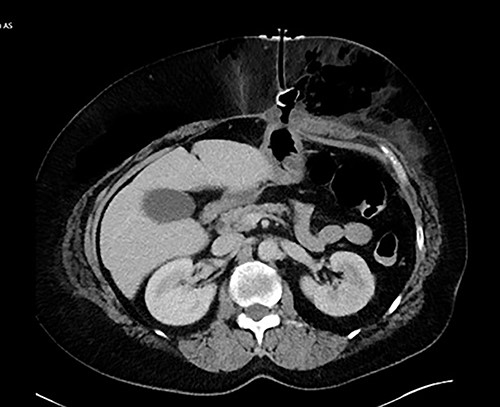

We present the case of a 60-year-old female who presented with a 3-month history of hoarseness and dysphagia in the setting of a left pyriform sinus hypopharyngeal lesion. The patient underwent evaluation in the operating room demonstrating deviation of the left arytenoid and aryepiglottic fold with associated enlargement and edema, prompting a tracheostomy placement in addition to lesion biopsy in order to secure a safe airway. The left pyriform sinus biopsy was remarkable for invasive, moderately differentiate squamous cell carcinoma. General surgery was consulted for placement of PEG tube secondary to high risks of aspiration and dysphagia caused by mass effect from the laryngeal cancer. A 20 French Corpak PEG tube was placed and secured with the internal retention bumper position appropriately against the gastric wall without tension; 2–0 prolene suture was utilized in order secure the bumper to the skin. Postoperative tube feeds were tolerated well and the patient was subsequently discharged from the hospital. The patient returned to the emergency department on postoperative Day 4 with complaints of significant, new onset abdominal pain. A computed tomography of abdomen and pelvis was obtained with evidence of BBS (Fig. 1). The patient was later taken to the operating room, where a laparoscopic gastrectomy was performed encompassing the necrotic portion of the stomach. The abdominal wall had developed an abscess in the left upper quadrant, prompting a laparoscopic 18F jejunostomy tube placement in order to avoid the previously involved region. The jejunum was then tacked to the abdominal wall and marked with 5 mm titanium endoclips in order to make replacement jejunostomy feasible with interventional radiology should the feeding access be dislodged. The abdominal wall abscess cavity measuring 30 × 20 × 10cm was appropriately debrided, the fascia approximated, and the wound closed with a negative pressure wound therapy (NPWT) device. The patient did inadvertently remove jejunostomy tube a few days later, which was replaced by interventional radiology. The patient tolerated tube feeds well and did not experience any other complications post operatively relating to feeding access. The NPWT sponge changes continued for ~2 months at which point the wound was amenable to simple packing and continued to heal appropriately.